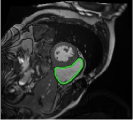

4.3 Comparison with cardic MR images for right ventricle segmentation

Cardiac MRI images often suffer from intensity inhomogeneity due to the varying magnetic susceptibility of cardiac tissues. This can lead to ambiguous boundaries, making it hard for models to consistently identify the left ventricle. Moreover, the heart is composed of several complex anatomical structures, including chambers, valves, and surrounding tissues. Accurately delineating the borders between these various components can be difficult, especially when they are closely positioned or exhibit similar intensity characteristics. In this section, we demonstrate the effectiveness of the RefLSM in segmenting cardiac MR images. The cardiac MR images are standardized to a size of . To enhance the credibility of the proposed model, we segmented 5 cardiac MR images compared the results with 6 other models, including the ALF [MA2019201], LoGRSF [DING2017224], ABC [WENG2021115633], RESLS[8765635], ICTM [WANG2022108794] and FeaACM [XUE2024110673] models. Fig. 5 displays the partial results from all the segmentation models. It is clear that the segmentation results from the RefLSM closely align with the ground truth of the left ventricle segmentation. However, the ALF model demonstrates relatively poor ability to capture the overall structure of the left ventricle; it exhibits limitations with precise boundary detection, particularly in areas of intensity inhomogeneity. Consequently, the evolution curve of the ALF fits into an unstable wave-like result. Suffering from intensity inhomogeneity and surrounding anatomical structures, the LoGRSF model, ABC model and RESLS model all represent over-segmentation and under-segmentation to some extent. Additionally, the results in the 6th column of Fig. 5 show multiple instances where where the ICTM model inaccurately identifies adjacent myocardial tissues as part of the left ventricle due to their similar intensity, leading to false positives. While the FeaACM demonstrates some ability to segment the left ventricle, it is not robust and fails to segment the 5th row of Fig. 5. The 2nd and 3rd rows also include small adjacent excessive regions. In contrast, our proposed model demonstrates marked improvements in accurately capturing the left ventricle’s boundaries. It effectively addresses challenges associated with severe intensity inhomogeneity and noise, resulting in better segmentations. The proposed method appear to maintain better structural integrity in the segmented images, closely aligning with the ground truth.

To quantitatively measure the segmentation results of each model, we compute the Dice and Precision values for left ventricle segmentation. Moreover, we opted for a voilin plot to effectively compare the RefLSM with six other models, as shown in Fig. 7. The results clearly demonstrate that the RefLSM yields superior Dice and Precision values than the other representative models, indicating its closer alignment with the ground truth and highest segmentation accuracy.